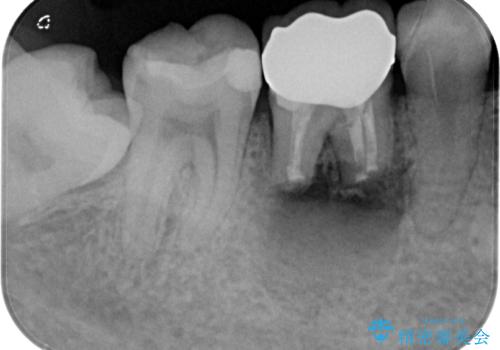

右下奥歯は既に根管治療が行われており、セラミッククラウンが装着されていました。

セラミッククラウンを壊して再度根管治療を行い、その後セラミッククラウンを装着する方法か、外科的に歯根の先端を切除し、炎症の原因である細菌を取り除き治癒を図る方法とを提案し、極力クラウンを壊さずに治療を進めたいとの希望により、歯根端切除術を行うこととしました。

治療から9か月ほどが経過した時点で、違和感や痛みはなく、歯根端切除術を行った右下は、レントゲンでも良好な経過が確認できました。

今後も継続して観察を行っていくこととなります。